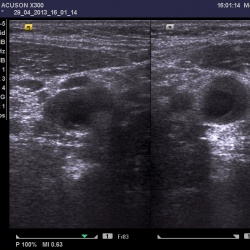

Коллеги, здравствуйте! Женщина, 55, рентгенолаборант. Образование в левой МЖ, очень переживает. Заключение рентгенолога - ФА, киста. Я ее посмотрела на УЗИ: ...

Образование молочной железы размерами около 11 мм в диаметре, не дающее акустической тени.Выполнена тонкоигольная аспирационная биопсия под УЗИ-контролем. Цитология рака молочной железы. Секторальная...